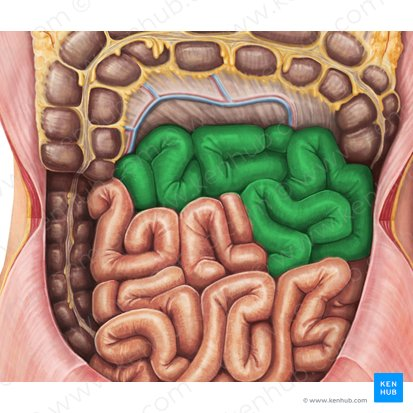

Jejunum

This is the middle section of the small intestine, and is characterized by numerous folds and villi, which increase the surface area for nutrient absorption.

Most of the absorption of carbohydrates, lipids, and proteins occurs

Mesocolon

A fold of peritoneum that attaches the colon to the posterior abdominal wall.

Right Colonic Flexure (Hepatic Flexure)

The bend in the large intestine where the ascending colon becomes the transverse colon, located on the right side of the abdomen.

Ascending Colon

The part of the large intestine that travels upward from the cecum along the right side of the abdomen.

Ileocecal Valve

A sphincter muscle situated at the junction of the ileum and the cecum, which controls the flow of chyme from the small intestine into the large intestine and prevents backflow.

Cecum

A pouch-like structure connected to the junction of the small and large intestines.

Appendix

A small, finger-like pouch attached to the cecum.

Ileum

The final and longest section of the small intestine, which absorbs vitamin B12, bile salts, and any remaining nutrients.

Jejunum

The middle section of the small intestine, where most of the digestion and absorption of carbohydrates, lipids, and proteins occurs.

Transverse Colon

The part of the large intestine that travels across the abdomen from right to left.

Left Colonic Flexure

The bend in the large intestine where the transverse colon becomes the descending colon, located on the left side of the abdomen.

Taenia Coli

Three longitudinal bands of smooth muscle on the outer surface of the large intestine that create haustra.

Descending Colon

The part of the large intestine that travels downward along the left side of the abdomen.

Haustrum